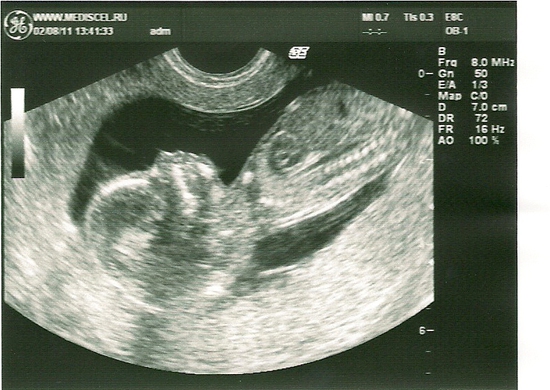

УЗИ, красотулька 14,5 недель.

Результаты: УЗИ, КТГ, доплера, скринингаСегодня сходила к своему любимому доктору на Узи. Вот результаты:

БПР 29 мм, лобно-затылочный размер 39 мм, окружность головы 107 мм, диаметр живота 27 мм, окружность живота 87 мм, длина бедра 14 мм, длина голени 12 мм, длина плеча 13 мм, предплечья 11 мм, КТР 85 мм. Сердцебиение 133 удара в минуту. Плацента по задней стенке, к дну, до 15 мм толщиной, 0-й степени зрелости. Вод умеренное колличество. Беременность 14,5 недель. Доктор сказал, что всё хорошо. Я счастлива. Вот моя красотулька.